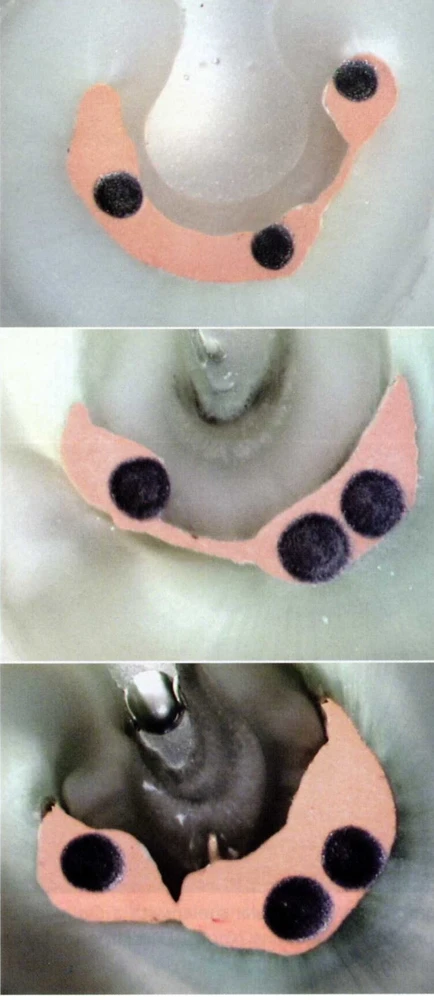

Để OB các răng CS ,lý tưởng nhất là dùng Thermafil cùng với Gutta được làm nóng chảy .

Hình ảnh một ÔT được OB bằng Thermafil+ GP lỏng ( nguồn : GUTMANN).